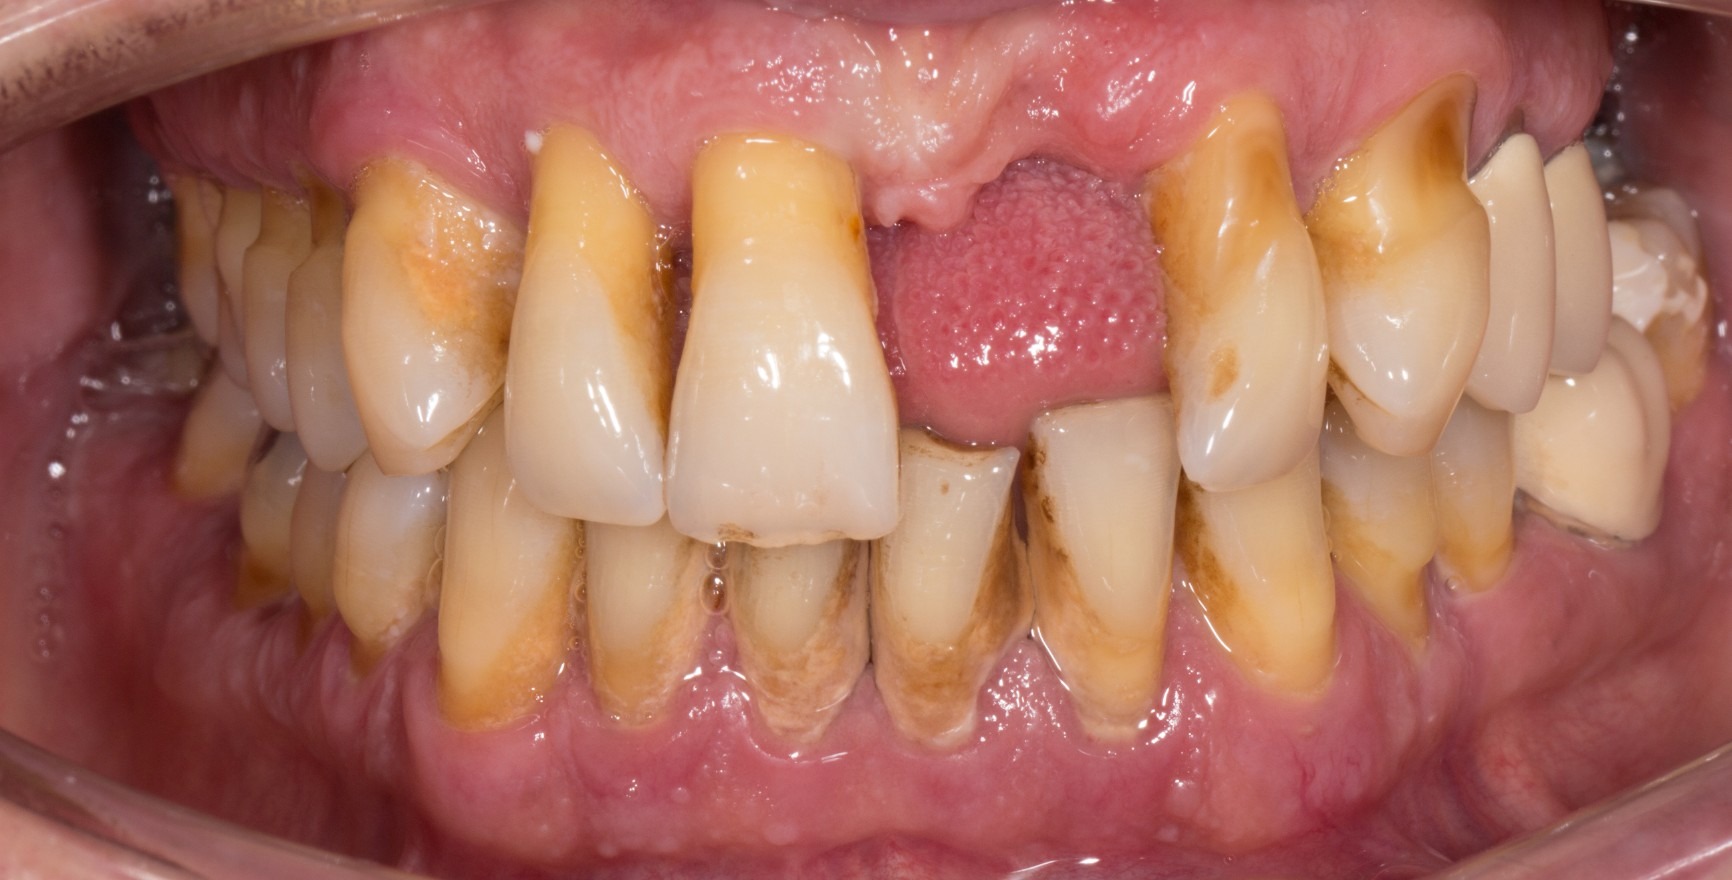

A state of clinical periodontal health in the intact periodontium is distinguished from that in a reduced periodontium already affected by clinical loss of attachment. This loss of attachment can occur:

as result of inflammation during the course of periodontitis. Clinical periodontal health then describes a stable condition after successful completion of periodontal treatment.

The clinical criterion is always the absence of bleeding on careful probing (bleeding on probing = BoP). A distinction is made between a site/tooth-specific diagnosis with a negative BoP finding at the corresponding measurement site, and diagnosis on the level of the tooth or patient, for which a threshold value of a BoP ≤ 10% still meets the criteria of clinical periodontal health. Pocket probing depths must be no more than 3 mm. In a reduced periodontium after periodontal treatment, a threshold value of 4 mm is still regarded as a stable status (Matuliene et al., 2008).